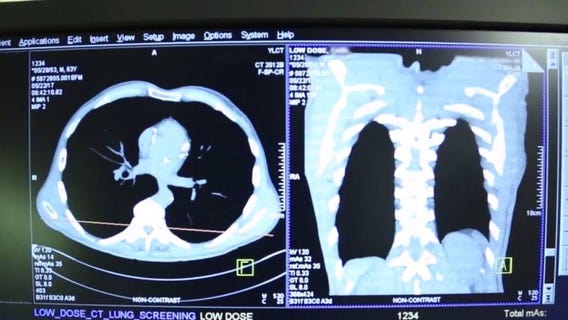

Lung cancer deaths outpace other major cancers as cases rise in young adults

Lung cancer is now the leading cause of cancer deaths in the United States, claiming more lives than several other major cancers combined.